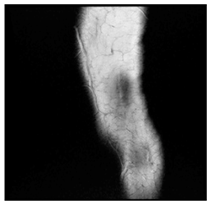

In this section, we present and analyze the results obtained with the proposed method, and compare it to methods proposed in similar works. The proposed watermarking system is implemented using MATLAB and executed on a Windows machine with the following characteristics: Intel R Core i5 processor, 4 GHz, 4 GB RAM, and Microsoft Windows 8 Professional operating system platform. In our experiments, we have used DICOM images of size 512 × 512 pixels as shown in Table 1.

Table 1.

Original images.